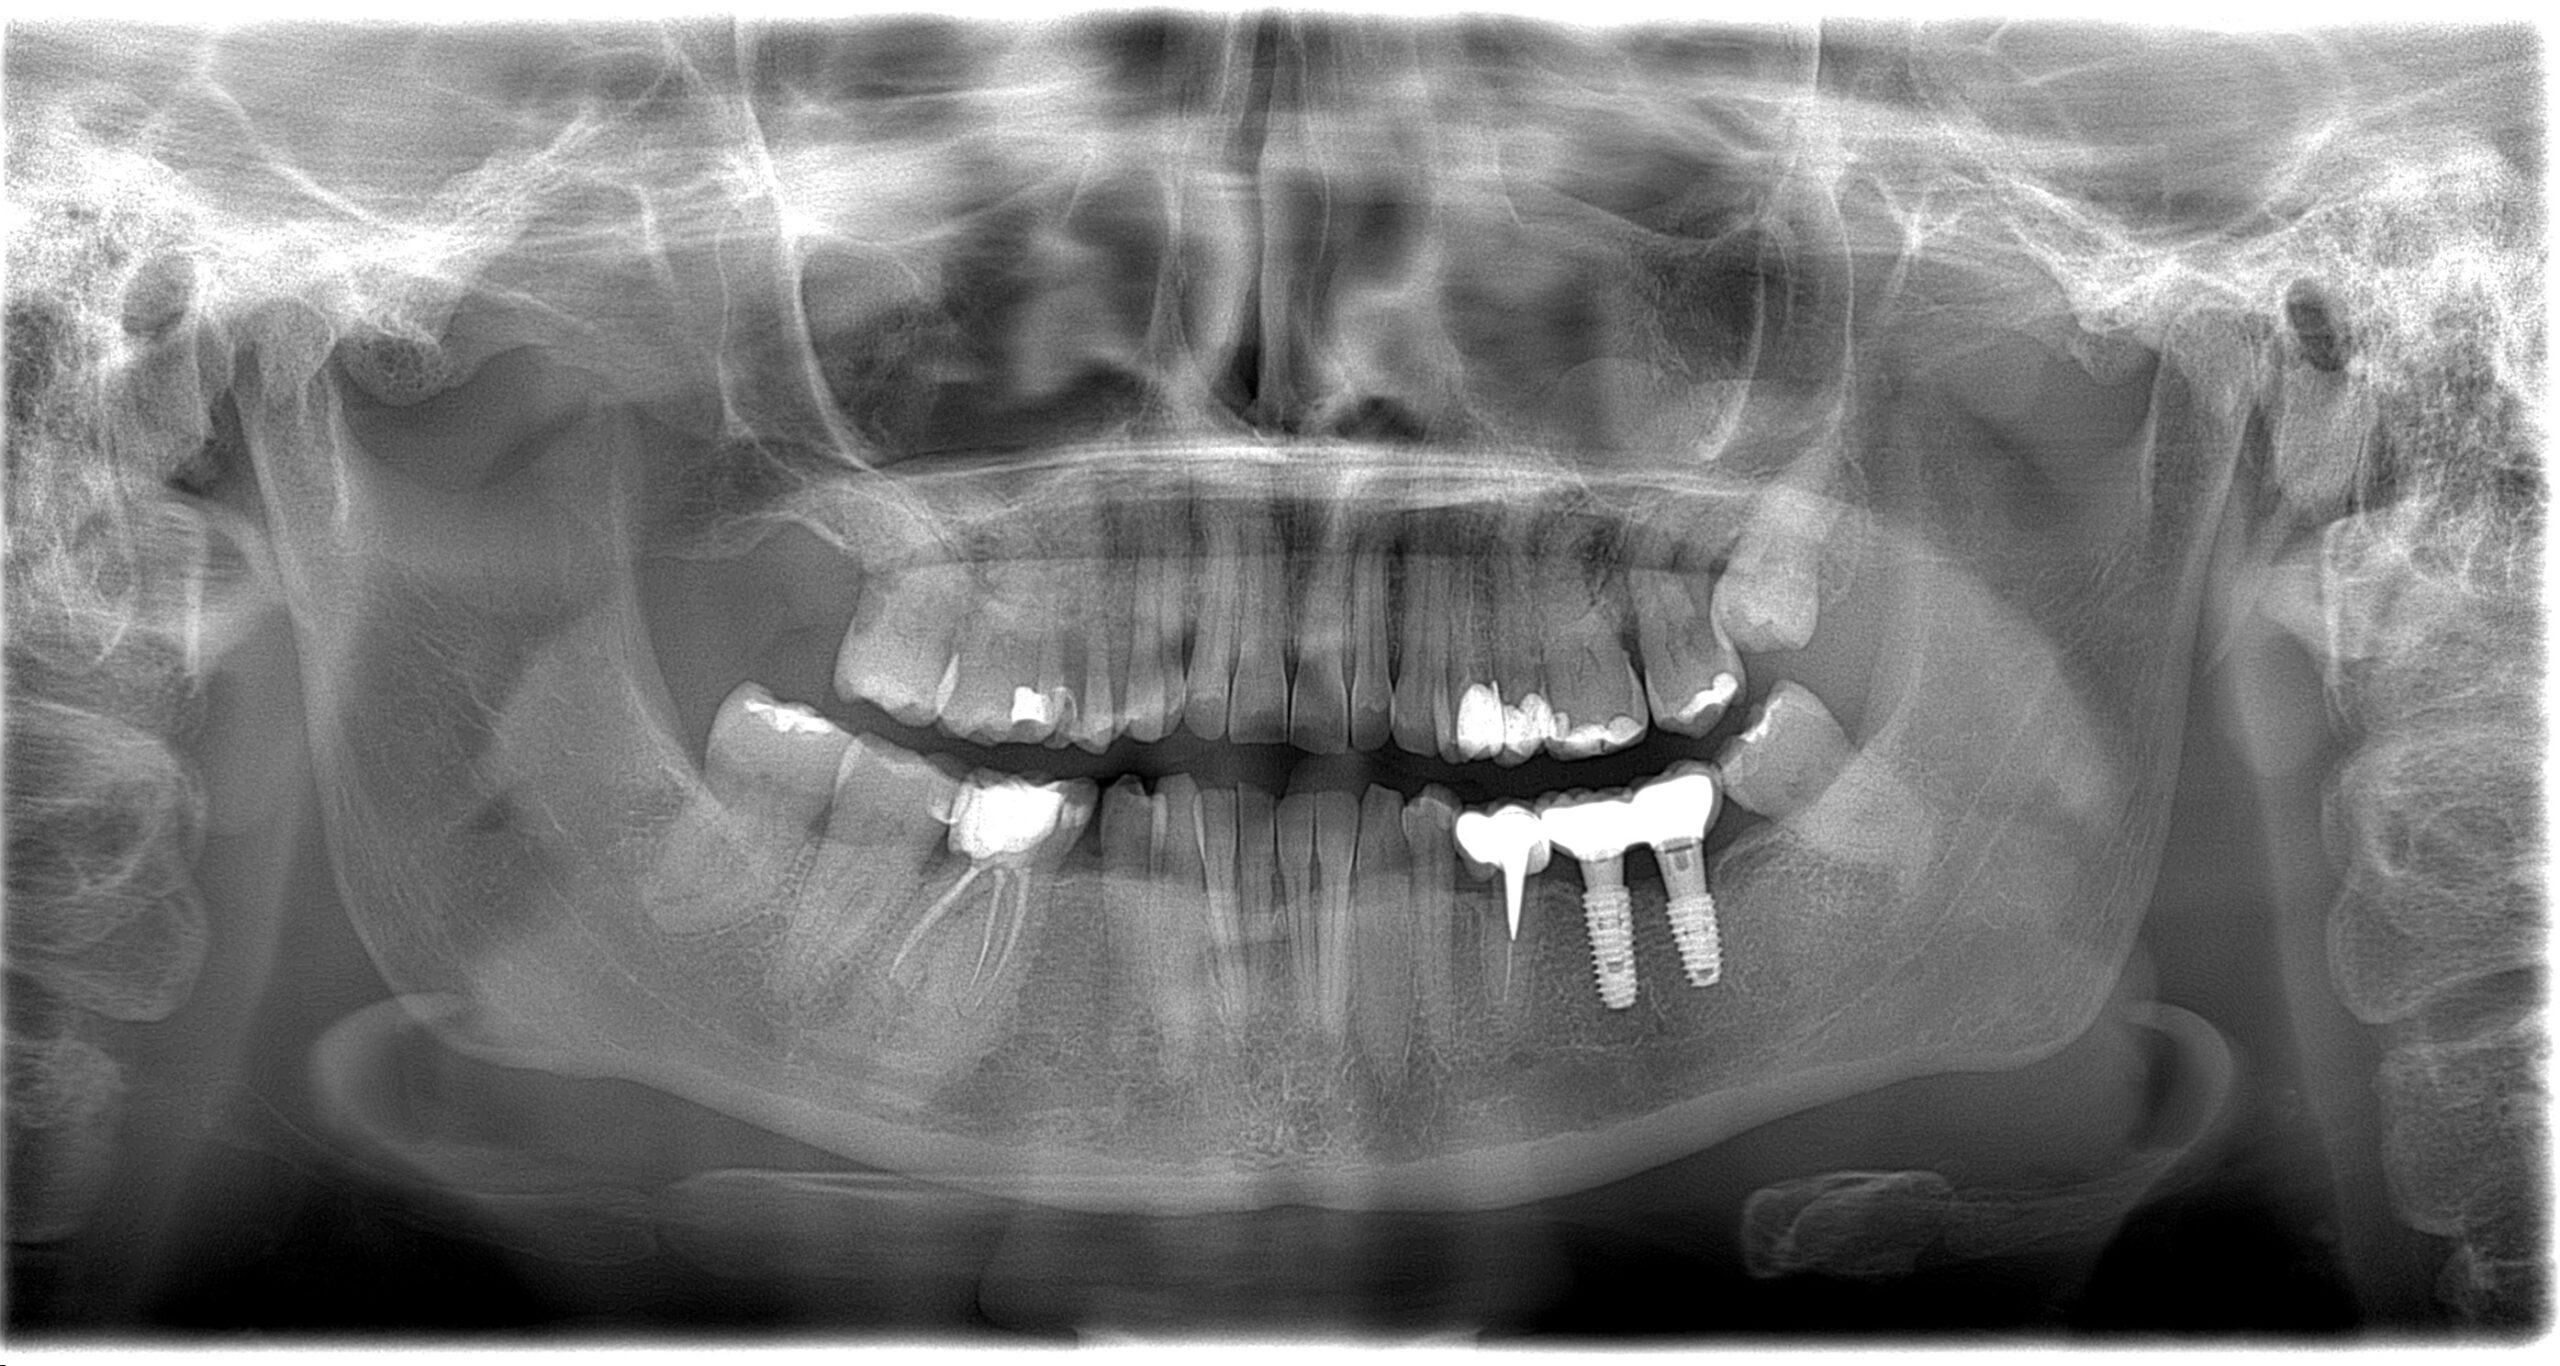

Імплантація